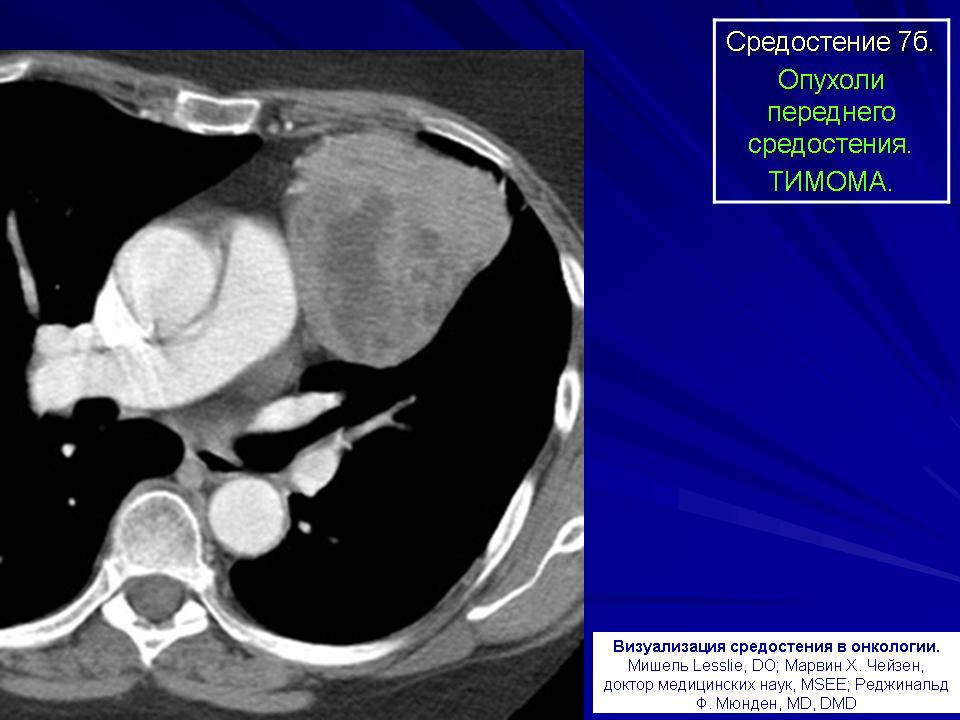

Тимома.

Рис. 2а,б,в,г. КТ-ангиография. В среднем и нижнем этажах переднего средостения неправильной формы, кистозно-солидной структуры, с четкими контурами образование, верхний полюс которого расположен под дугой аорты, а нижний достигает диафрагмы. На фоне введения контрастного вещества неравномерно повышает свою плотность. Бифуркация трахеи, левый главный бронх, легочная артерия умеренно оттеснены вправо.

Заключение: тимома, учитывая четкие контуры, вероятнее всего, доброкачественной природы.

Гистологическое исследование послеоперационного материала - тимома, тип АВ.